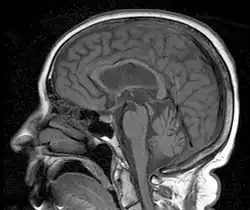

Die progressive supranukleäre Blickparese (progressive supranuclear palsy, PSP; auch progressive supranukleäre Paralyse, Steele-Richardson-Olszewski-Syndrom) ist eine degenerative Erkrankung des Gehirns, speziell der Basalganglien. Die Basalganglien sind Bereiche im Gehirn, die eine wichtige Rolle bei der Steuerung automatischer Bewegungen spielen. Ihre Schädigung kann zu Problemen beim Bewegen und beim Halten des Gleichgewichtes, bei der Augensteuerung, der Schlucksteuerung und der Sprechsteuerung führen. PSP ist verwandt mit der Parkinsonschen Krankheit, die Krankheiten ähneln sich in vielen Symptomen. Nicht selten wird die geringer verbreitete PSP für eine Parkinson-Erkrankung gehalten. PSP wird mit anderen Parkinson-ähnlichen Erkrankungen unter dem Begriff atypische Parkinson-Syndrome oder Parkinson-plus zusammengefasst.